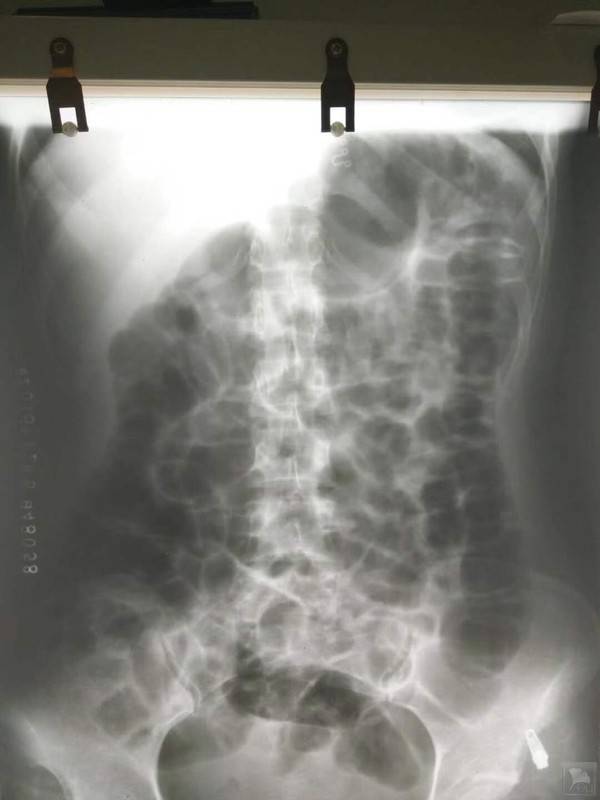

患者刘某,女,24岁,反复嗳气、腹部胀痛2月余,2月前因情绪不佳和饮食不规律出现嗳气,反酸,腹部胀痛,排气增多,症状呈进行性加重,先后服用“吗丁啉、雷尼替丁、莫沙必利”,症状仍持续加重,于2018-11-28到广东省第二人民医院就诊,行腹平片示“肠管普遍大量积气”,腹部彩超示“少量盆腔积液”,胃镜示“浅表性胃炎,HP(+)”。血常规、生化、肝肾功能、风湿11项、胃泌素、肝吸虫、大便培养扥检查未见明显异常。服用4联抗HP药物治疗2周,前3天症状缓解,后症状反复,2019-12-8因腹痛剧烈行腹部增强CT检查示:“胃肠道大量积气,少量积液,未见明显肠梗阻、气腹征象”。曾在中山附一、附三、广药附一等医院就诊,先后服用“泌特、美常安、西甲硅油、多酶片、金双歧、黛力新、左氧氟沙星片,2周健胃行气中药”等,症状时轻时重,晨起轻,下午晚上加重。2019-1-10行肠镜检查未见异常,全部停药,但症状仍时轻时重,患者起病以来,精神欠佳,食欲减退,嗳气,腹部胀痛,排气及大便次数增多,小便正常,体重减轻8斤。舌淡红,苔薄腻,脉弦细。

客观检查结果: